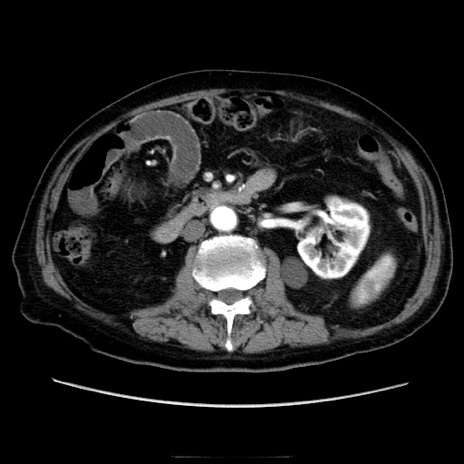

症例21(横断像)

【症例】70歳代男性

【主訴】腹痛

【現病歴】肝硬変・肝細胞癌にてかかりつけの方。約9時間前に食後より腹痛出現。症状が徐々に増悪し、嘔吐出現したため来院。

【既往歴】肝硬変、肝細胞癌(RFA、TACE後)

【身体所見】意識清明、表情苦悶様、BT 36℃、BP 129/78mmHg、P 88bpm、SpO2 97%(RA)、右上腹部から心窩部にかけて圧痛あり、反跳痛なし、筋性防御あり。

【データ】WBC 5800、CRP 0.16